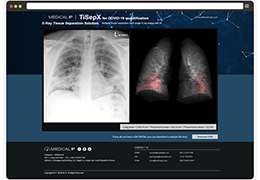

View X-Ray CT & MRI Scans Fast and Easily

Designed for surgeons, Pro Surgical 3D makes it easy to view patient scans quickly. Pro Surgical 3D facilitates the optimal 3D treatment and assessment workflows based on X-ray CT and MRI scans – and best of all, it’s FREE!

High-quality and fast 3D reconstruction and 3D rendering

Side-by-side comparative assessment for pre- and post-operative scans.